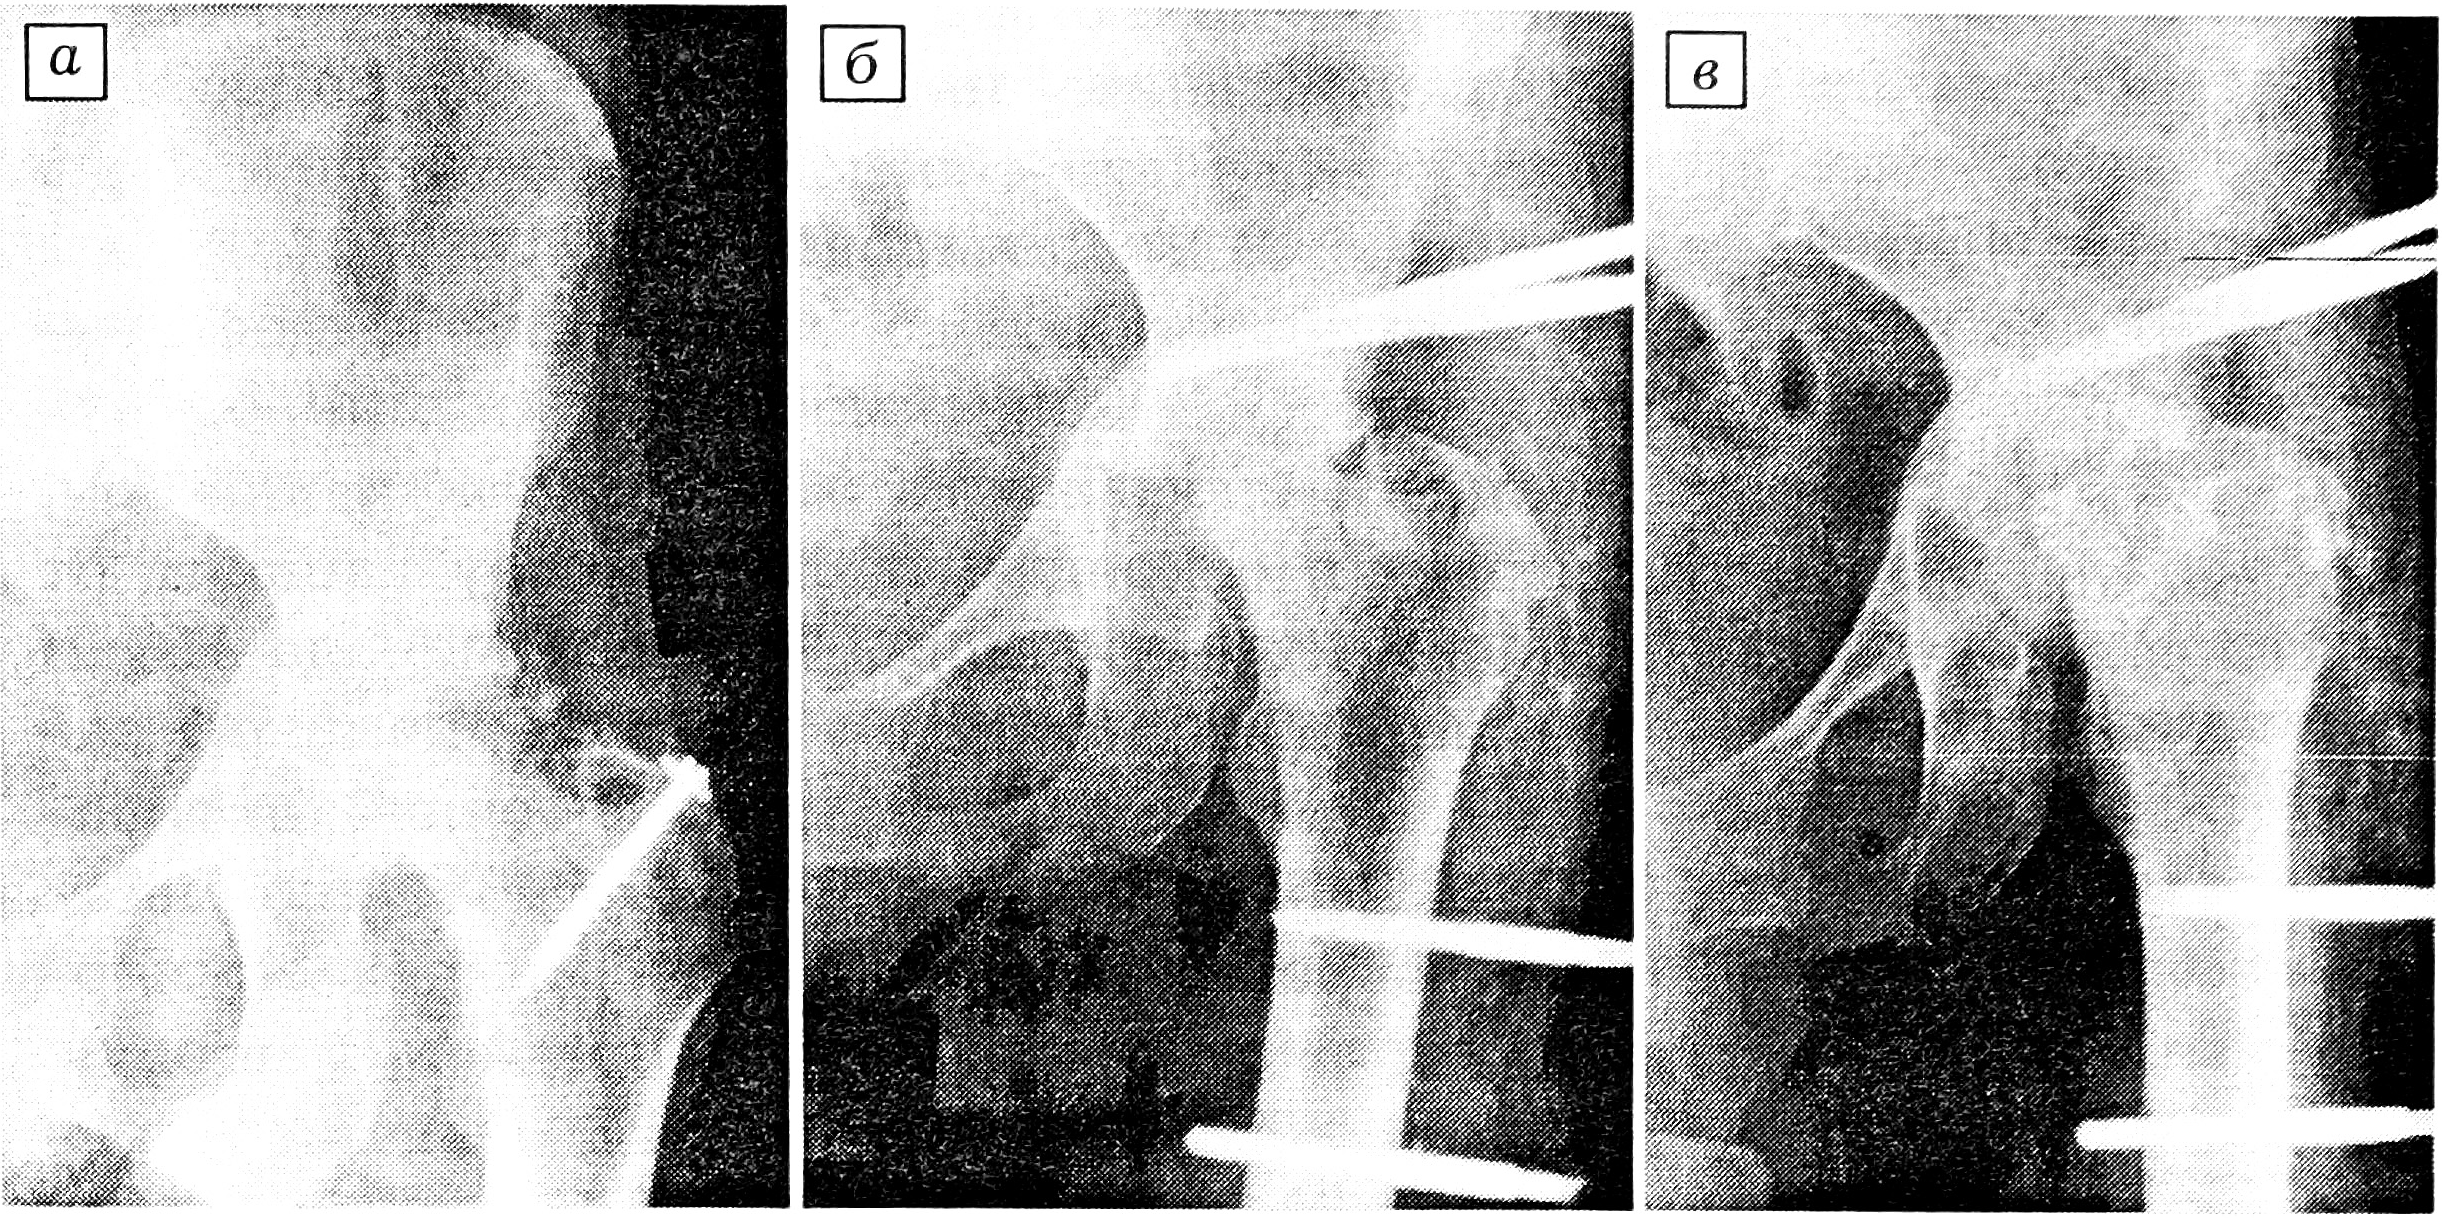

Больная Н., 43 лет, инвалид II группы, поступила в клинику артрологии Саратовского НИИТО 3.12.93 с диагнозом: посттравматический асептический некроз головки бедренной кости IV степени, состояние после открытого вправления вывиха бедра, произведенного в ноябре 1992 г. (рис. 1, а). 23.12.93 выполнена операция артродезирования тазобедренного сустава с использованием стержневого аппарата (рис. 1, б). Через 6 мес после операции отмечено образование костного анкилоза (рис. 1, в) и фиксация стержневым аппаратом прекращена. Через 8 мес после операции боли и подвижность в суставе отсутствуют, больная ходит с опорой на трость, особых затруднений в самообслуживании не отмечает. Инвалид III группы.

Рис. 1. Рентгенограммы тазобедренного сустава больной Н.

a — при поступлении;

б — непосредственно после операции артродезирования с использованием стержневого аппарата;

в — через 6 мес после операции.